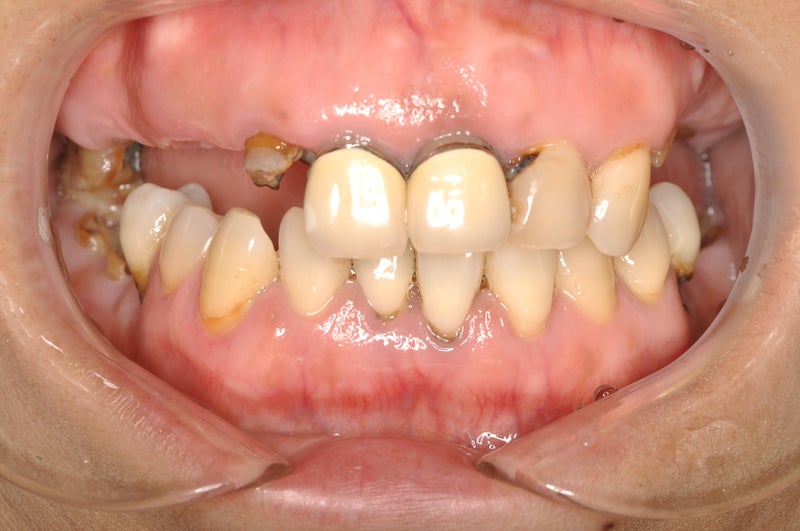

<before>

▶︎そのため、歯の頭が溶けてしまったり、歯茎が下がってしまったりと審美的にも噛み合わせ的にも悪い状態で当院に来院されました。